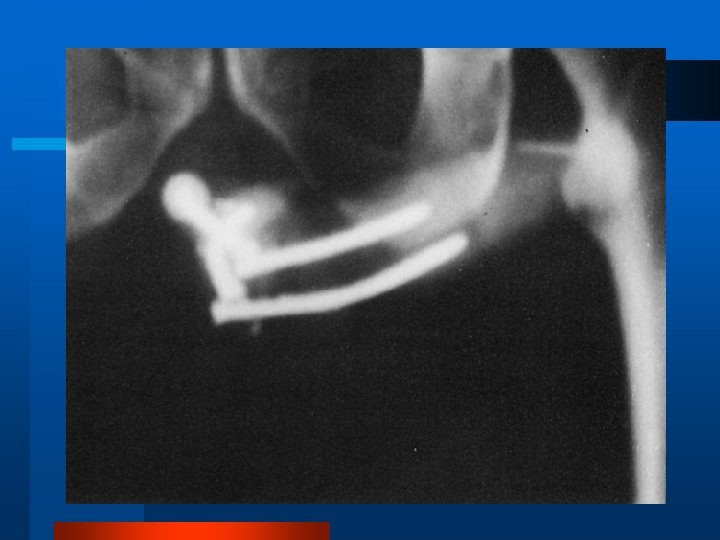

Próteses Penianas - Tipos l Maleáveis l Infláveis ou semi-rígidas

Próteses Penianas Infláveis l Cilindros, preenchidas por líquido – Líquido armazenado no próprio cilindro

Próteses Penianas Infláveis l Cilindros, preenchidas por líquido – Líquido armazenado no próprio cilindro (self -contained) Dinaflex-MAS – 2 ou 3 peças, com um reservatório ligado ao cilindro – 2 peças (Ambicor -MAS e Mark II -Mentor) – 3 peças (MAS 7 W e Alpha-1 Mentor)